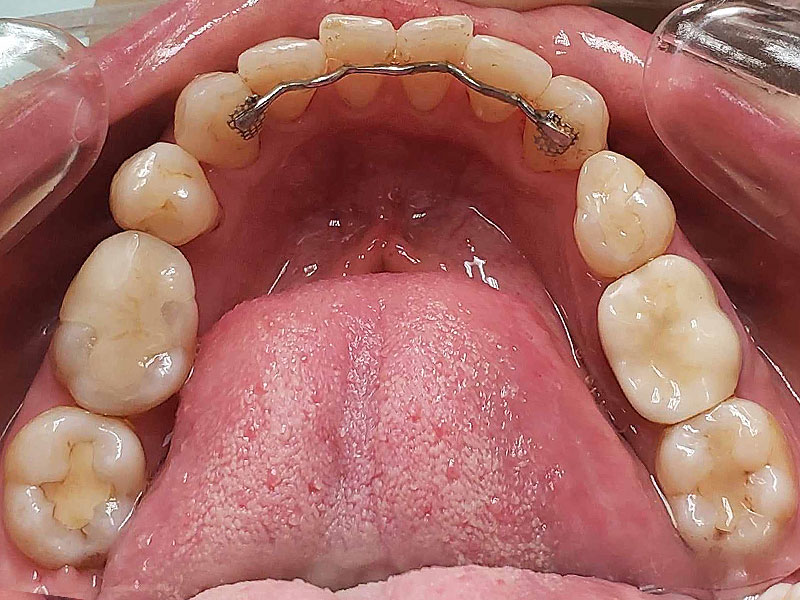

術後

約2年治療期間で包括矯正治療は完結となり、患者さんは大変満足してくれました。更にかみしめ癖も軽減し、肩こりも無くなったとのことです。口腔内写真からも舌房が確保され、舌圧痕がなくなり、かみしめ癖が軽減したことも十分にわかります。

(注、矯正治療して歯並びを治したら、肩こり、不定愁訴がなくなるわけではないことは断言しておきます。かみしめ癖が無くなっただけです。)

術後10年後

着色は認められますが、ほぼ10年前の状態を維持しているように思えます。着色したCRをセラミックにという考え方もありますが、神経除去のリスクもあるため、患者さんが見た目でどおしてもと希望されないかぎり、個人的にはお勧めしません。この方も希望されませんでしたが、症状を訴えたり、確実に中が虫歯と判断しない限り、このまま経過観察していこうと考えています。